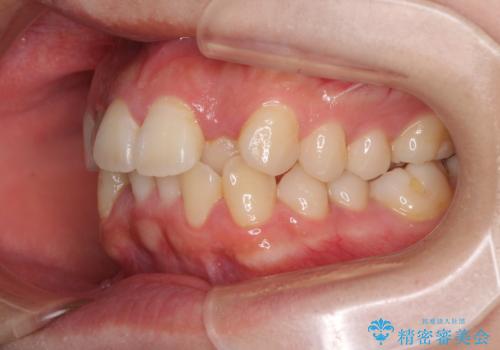

- 上下のデコボコと前歯のクロスバイトを改善したいとのことで来院された患者様です。

極力短期間で治療したいとのことで、ワイヤー装置による矯正治療を行うこととしました。

マウスピースによる矯正治療も提案しましたが、ご自身でのマウスピースの管理の面倒くささと、なるべく早く治療を終えたいとのことで、ワイヤー矯正を選択されました。